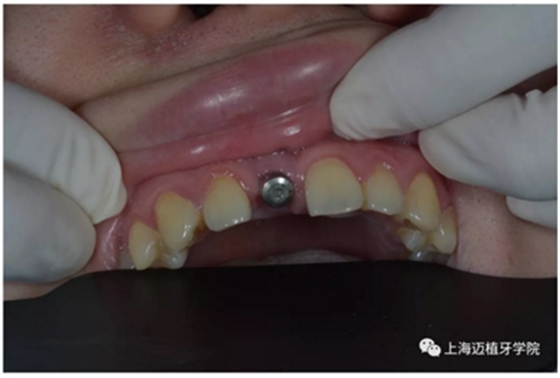

戴牙前口內(nèi)照片:

去除愈合基臺: